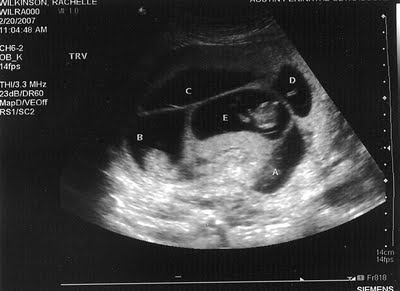

Incredibly, the treatment worked and Rachelle was pregnant. The couple were very excited and began preparations. The pair were secretly hopeful for twins, but nothing could prepare them for what the first ultrasound had in store for them.

During their ultrasound the doctors found a third heartbeat. The room erupted up with excitement but then the doctors found more. It turned out that Rachelle and Jayson were about to have five babies! Rachelle wrote on her blog about the incredible experience of hearing the news.